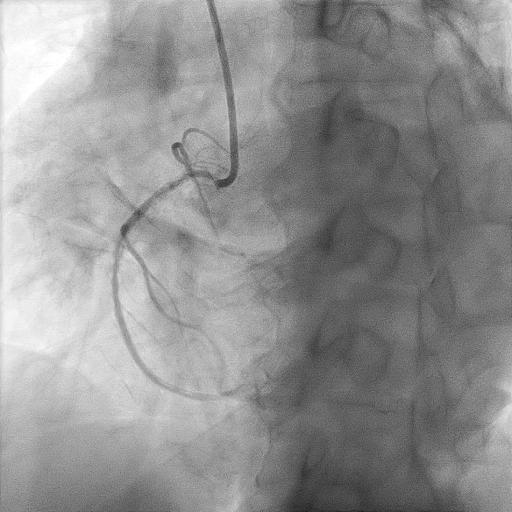

Now for staged PCI to RCA. Attempted engagement with a JR 3.5 6Fr via RRA.Challenges anticipated:1 subclavian tortuosity, noted from past angiography – needing gentle manipulation, avoid femoral access2 poor engagement due to ostium disease3 wiring from outside ( ¡®air-mail¡¯)Lesions are calcifed, diffuse, proximal(ostium RCA) and distal to stented segment - stent not covering ostium.Plan is to IVUS, prepare new lesions, prepare ISR segments then either hybrid DES/DEB or new DES all the way.

Airmail wire into RCA.wmv

Challenges:1 During PCI, ostium lesion causes BP dampening + ST elevations - catheter kept outside ostium during entire PCI2 Wiring was done from outside - 'air mail'ed into the RCA3 Long stent needed delivering - used 'buddy wire' technique to deliver this4 Findings exact ostium was tough - 'buddy wire' converted to 'sepal wire' for better outcome5 During postdilatation, the 'stubborn' nodule at the distal part of stent, was difficult to prepareEven after stenting, IVUS improvement only. Stent boost was used to delineate the calcific nodular area.